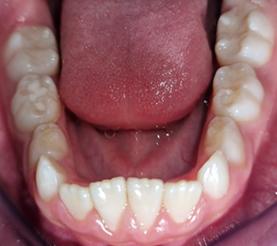

Est. Nicole Emily Rojas Espinoza1 Dr. Juan Pablo Torrico Vilte2

1 Estudiante, Carrera de Medicina, Universidad Privada del Valle. Sede Cochabamba, Bolivia. ren2015280@est.univalle.edu 2Docente, Carrera de Medicina, Universidad Privada del Valle. Sede Cochabamba, Bolivia. jtorricovilte@gmail.com

Recibido:5/1/2023 Revisado:10/5/2023 Aceptado:10/5/2023

Cita: Est. Nicole Emily Rojas Espinoza, Dr. Juan Pablo Torrico Vilte; Cirugía más inmunoterapia local en el tratamiento del tumor de Buschke-Löwenstein. A propósito de un caso. Revista De Investigación E Información En Salud UNIVALLE 2022; 18(44): p.49-53 https://doi.org/10.52428/20756208.v18i44.448

Correspondencia: Est. Nicole Emily Rojas Espinoza, Cochabamba, Bolivia, +591 70797928 ren2015280@ est.univalle.edu

Nota: Los autores declaran no tener conflicto de intereses con respecto a esta publicación y se responsabilizan de contenido vertido.